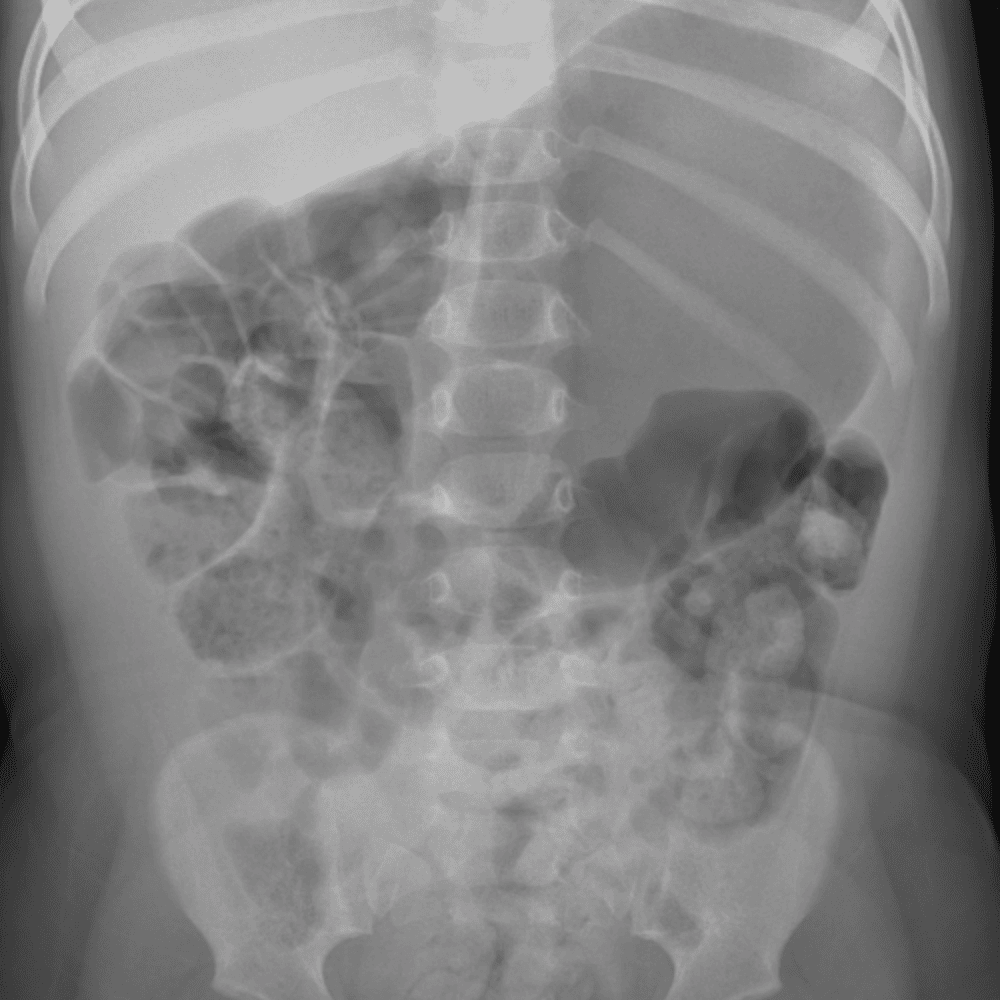

Peds Abdomen

Practice

Simulates call by including subtle or difficult cases and some normals.

30 cases